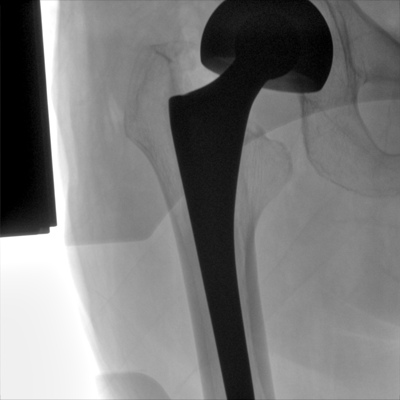

大尺寸液晶顯示器,圖像顯示清晰細膩;顯示器可大角度旋轉,滿足臨床多角度觀察圖像的需要。